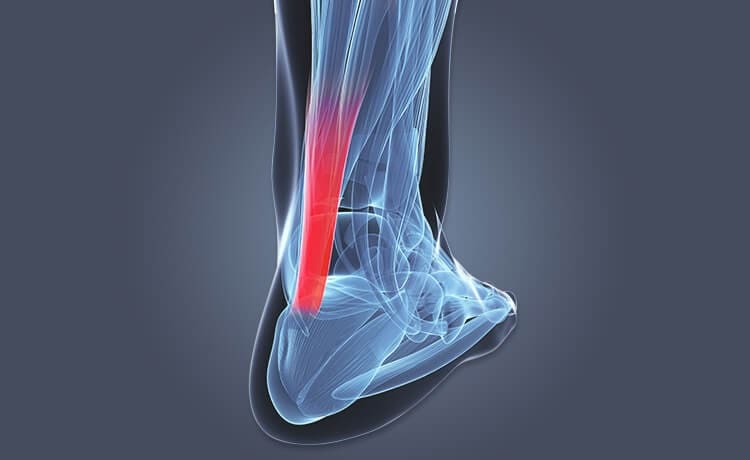

Located on the sole of the foot, which runs from the toes to the heel is a thick, fibrous band of tissue known as the plantar fascia and in some instances can become irritated. There are a number of muscles that act around the ankle joint to help perform the available movements, these include:

- Gastrocnemius (calf muscle)